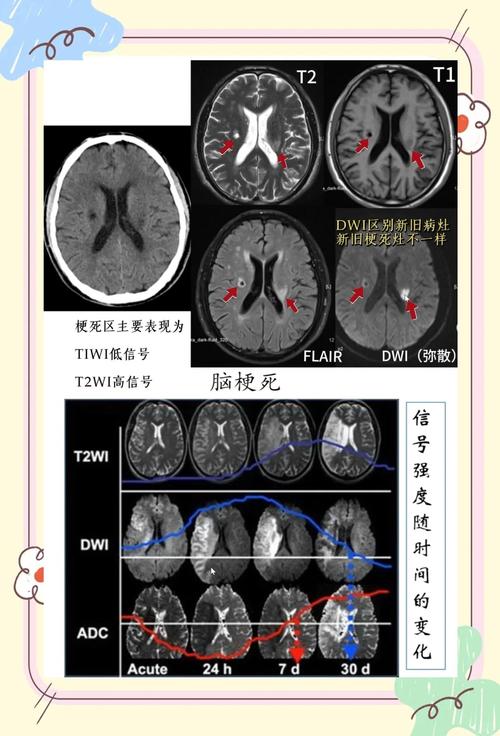

DWI可以在发病后数分钟内就发现缺血坏死的区域,比传统的CT和常规MRI(如T1、T2加权像)要早得多(通常早2-4小时)。 这为“时间窗”内的治疗提供了决定性的影像学依据。

DWI上看到的表现是什么?

当医生怀疑急性脑梗时,会开具头颅MRI检查,并特别关注DWI序列及其衍生序列ADC (Apparent Diffusion Coefficient)。

- DWI图像:在急性梗塞灶区域,会看到清晰、明亮的高信号(白色)病灶,这个病灶的大小和位置直接反映了缺血坏死的范围。

- ADC图像:这是DWI的“反向”图像,直接反映水分子扩散的程度,在急性梗塞灶,由于水分子扩散受限,ADC值会降低,因此在ADC图像上,同一个病灶会显示为低信号(黑色)。

“DWI高信号,ADC低信号”是急性期(超早期)脑梗塞的典型特征性表现,具有很高的特异性。

- 发病1-2周后:梗塞中心的脑细胞已经液化坏死,水分子又可以自由运动了,DWI上的高信号会逐渐消失,病灶可能变为等信号或低信号,而在T2/FLAIR序列上会变为永久性的高信号(软化灶)。

- 发病数周至数月:病灶进入慢性期,DWI通常为等信号,与周围脑组织难以区分。

- 在某些情况下,比如慢性、陈旧性的梗塞灶,在T2加权像上本身就是高信号,这种高信号也会“穿透”到DWI图像上,造成假阳性的假象。

- 鉴别方法:一定要看ADC图像,如果是T2穿透效应,ADC值是正常或增高的(在ADC图上是等信号或低信号),而真正的急性梗塞ADC值是降低的(在ADC图上是低信号)。